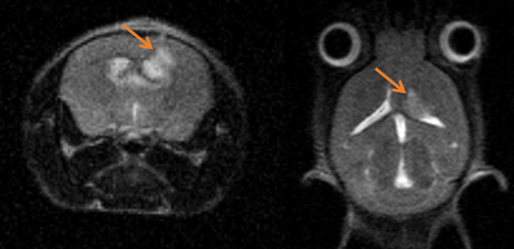

Monitoring tumor growth in the mouse brain, following the orthotopic injection of glioblastoma cells, using T2-weighted images. Image Credit: Scintica Instrumentation Inc

Multimodal imaging combines the strength of MRI with other imaging modalities, such as PET and CT. PET provides information on the spatial distribution of molecular signal of interest. In this case MRI confirmed that the absence of tracer uptake in the center of the images was due to the presence of a necrotic core, which appears hyperintense on T2-weighted MR. Image Credit: Scintica Instrumentation Inc

Multimodal Imaging: Multimodal imaging combines the strength of MRI with other imaging modalities such as PET and CT. PET provides information on the spatial distribution of molecular signal of interest. In this case MRI confirmed that the absence of tracer uptake in the center of the images was due to the presence of a necrotic core, which appears hyperintense on T2-weighted MRI. Image Credit: Scintica Instrumentation Inc